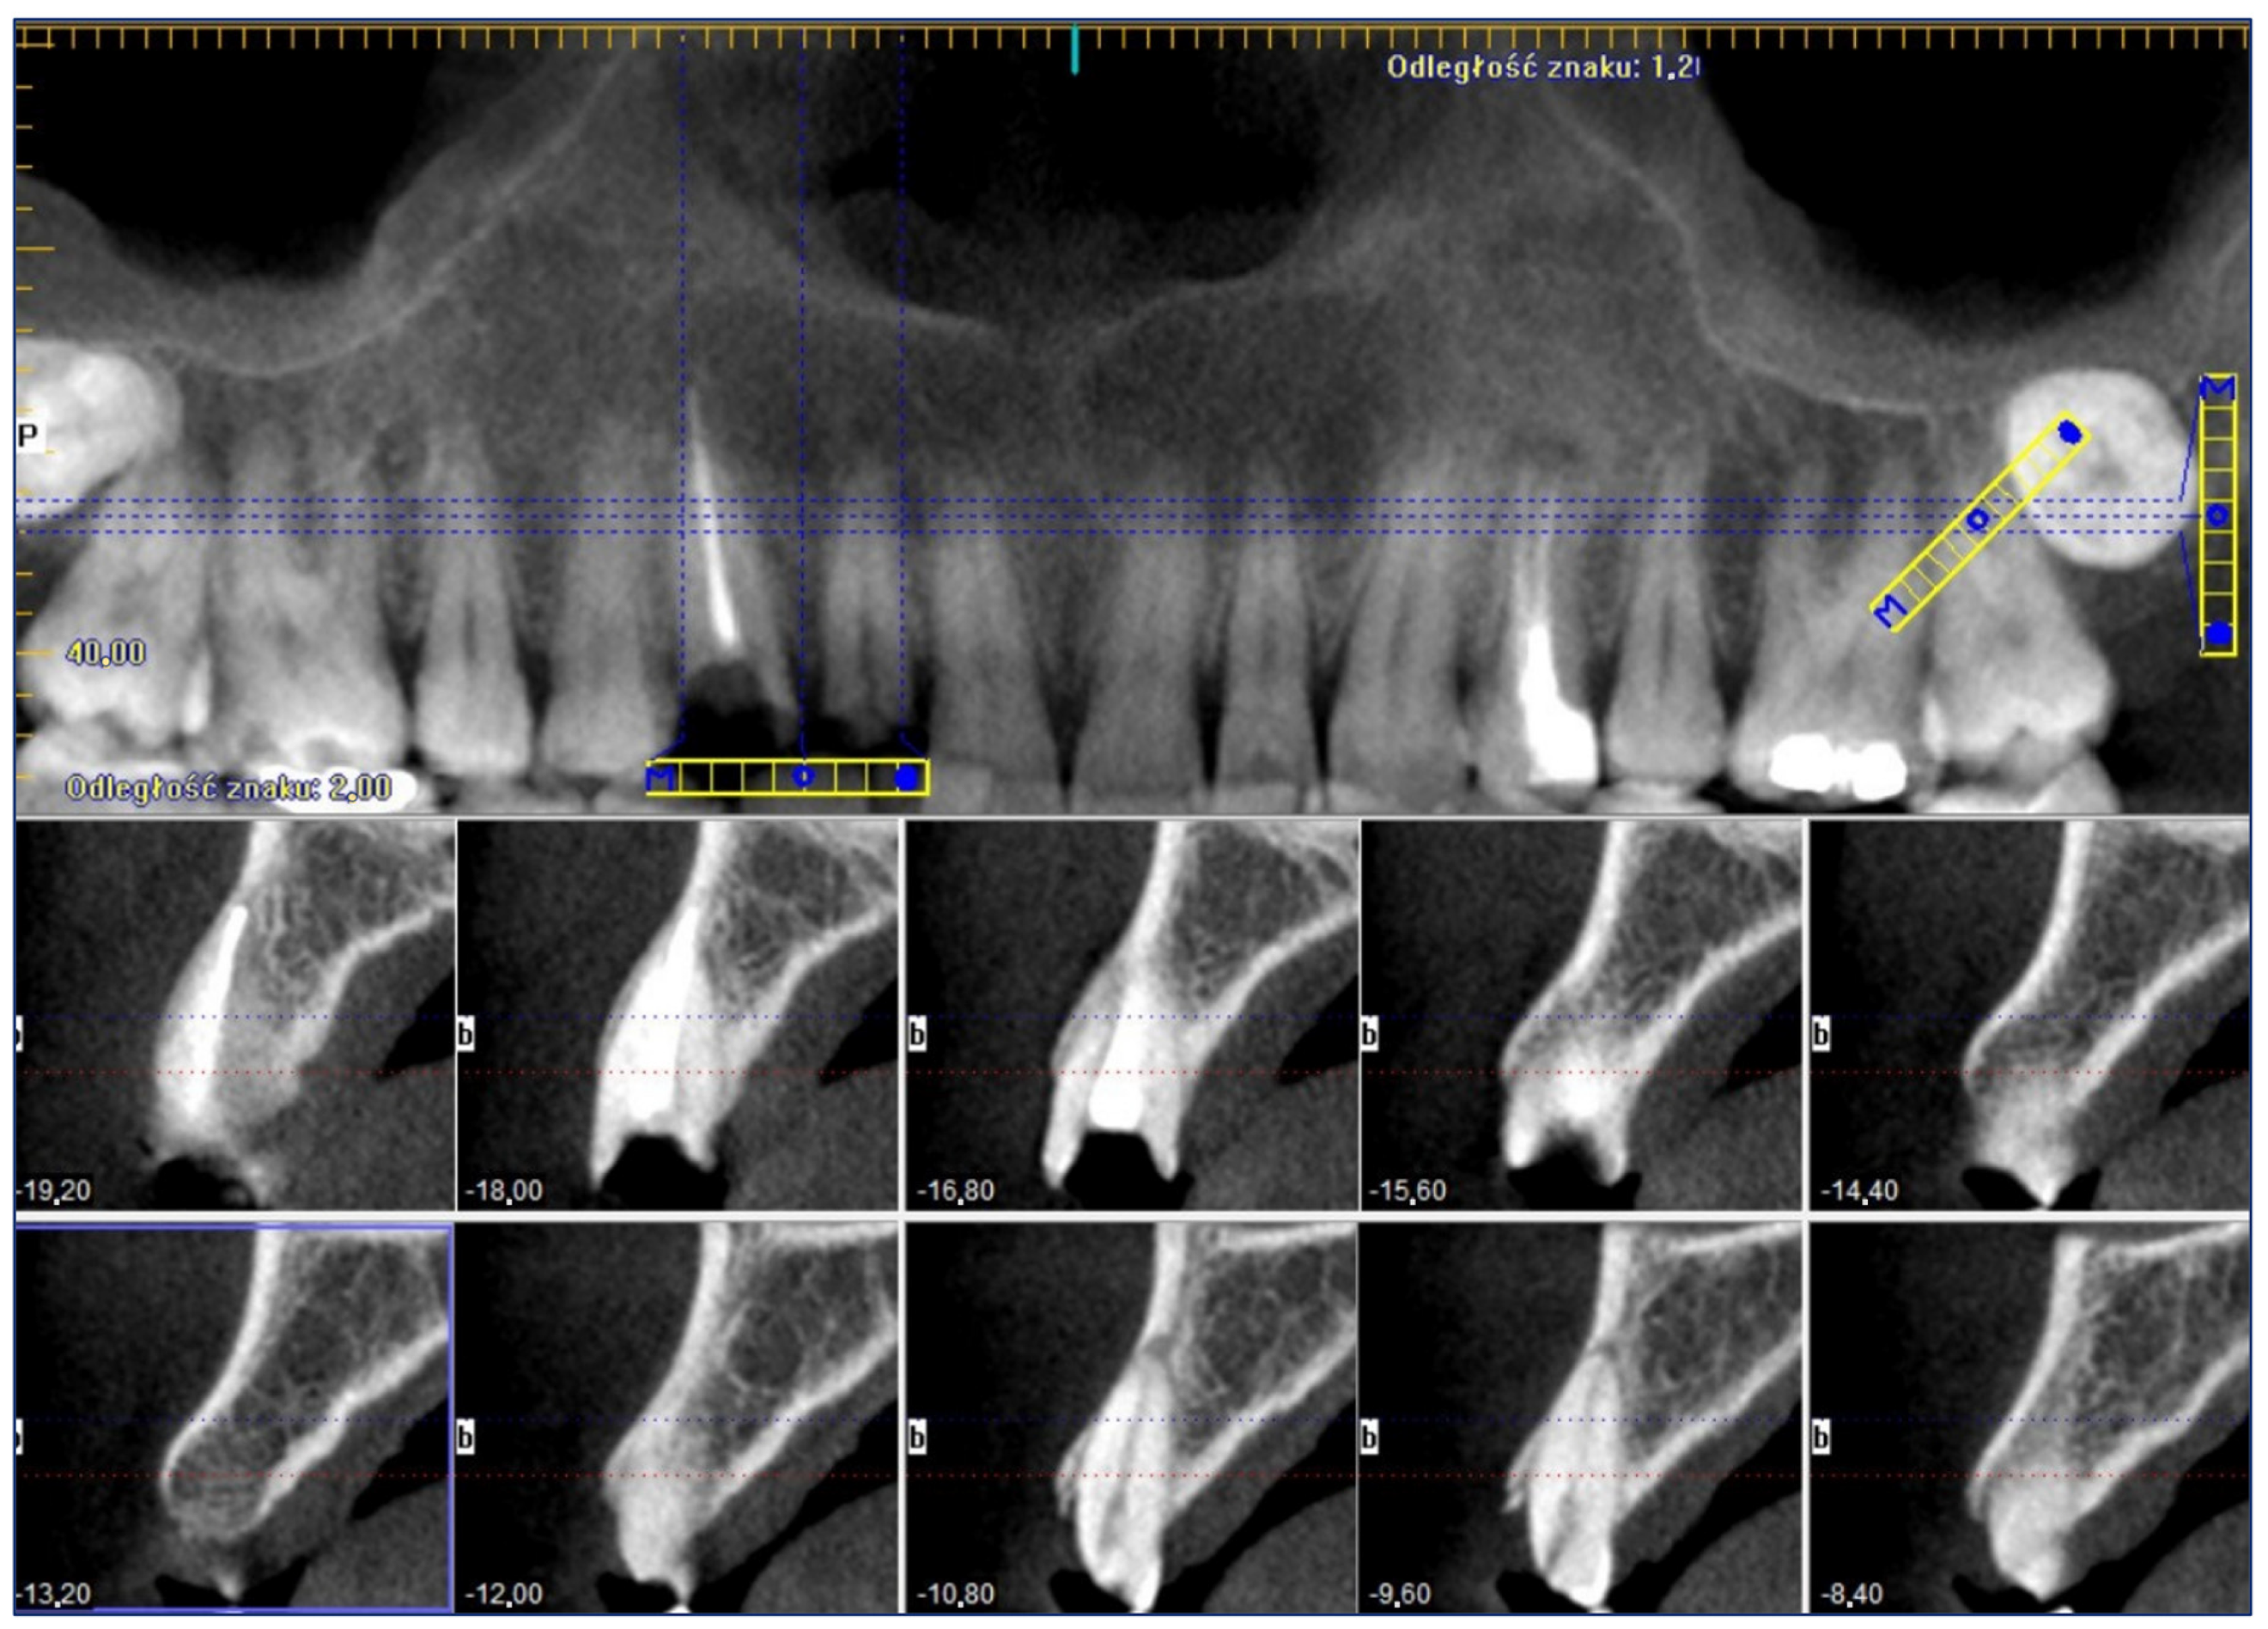

3.2. Surgery